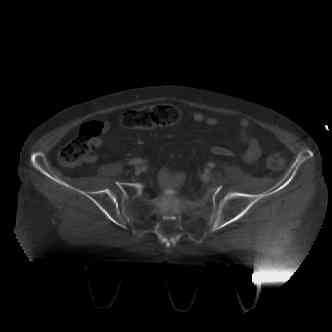

attached are images of a 70 year old female after peds versus car. her own car ran her over.

injuries are limited to the pelvis. left rami open and visible in a 10cm vertical laceration just lateral to left labia majora. wound is grossly clean. no vaginal and no urinary issues. CT scan shows widening of both SI joints anteriorly but I think this is vertically stable pattern.

pt treated that night with I/D and supra-acetabular frame to close the ring. consideration was given for SI screws bilateraly, but given time of night and other factors decision made not to proceed.

so the question is what next operatively if anything? concerns are infection, nonunion anteriorly and possible incompetence of the pelvic floor which may lead to prolapse issues. right rami are comminuted and plating may entail ilioinguinal approach to extend plate laterally to right iliac wing. retrograde screw up right rami is an option but I am not convinced it will add much. adding SI screws very doable, but major concern is restoring anterior ring. so far wound is clean and closed over a drain, and I have no plans to open it back up and wash again.

maintaining pelvic alignment in ex-fix in 70 yo female for any length of time may be challenging.

any thoughts? would anyone plate the pubic symphysis to close the gap and leave the more lateral rami fractures alone? the most recent pelvic case on this website involved pts with suprapubic catheters and antibiotic options including resorbable beads. I wonder how many people would plate and place antibiotic beads. thanks.

We'd need ct images to make reasonable recs.

Chip

attached are several CT cuts. please let me know if you need more. the CT is pre-pelvic ex-fix placement.

Thank you.

I wouldn't plate the front.

But I would add screws posteriorly.